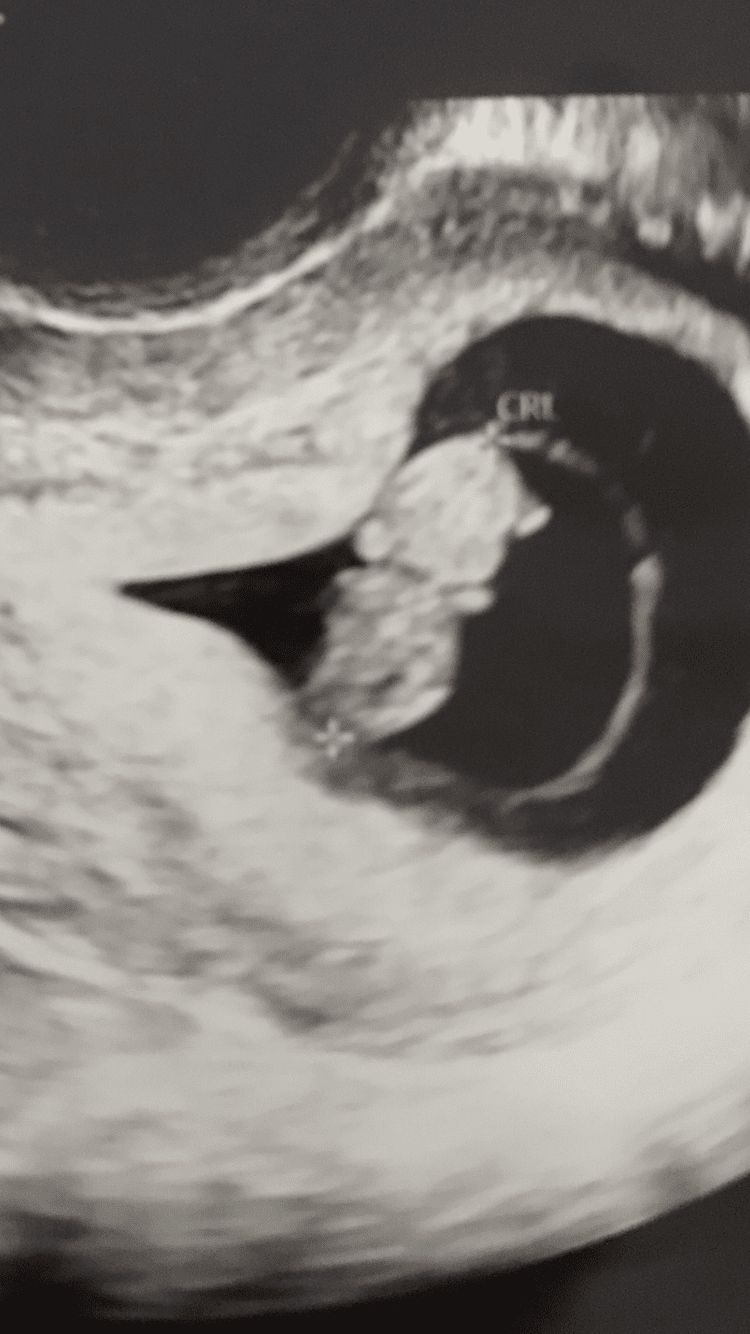

Wróciłam z wizyty. Ciąża jednak starsza termin 16.12 a nie 18.12 😁

Serducho bije pięknie 181 uderzeń na minutkę i ta dzidzia jakaś taka już nawet ludzka w wyglądzie ❤️

Tak jak spojrzałam pomyślałam - jakie ładne dziecko ❤️🥰🤪